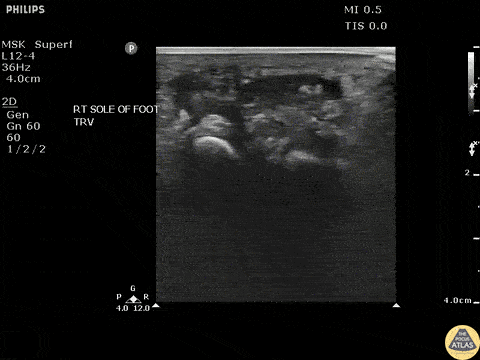

Soft Tissue - Toothpick Foreign Body

Transverse view of a toothpick foreign body exhibiting posterior acoustic shadowing. Image courtesy of Robert Jones DO, FACEP @RJonesSonoEM Director, Emergency Ultrasound; MetroHealth Medical Center; Professor, Case Western Reserve Medical School, Cleveland, OH View his original post here